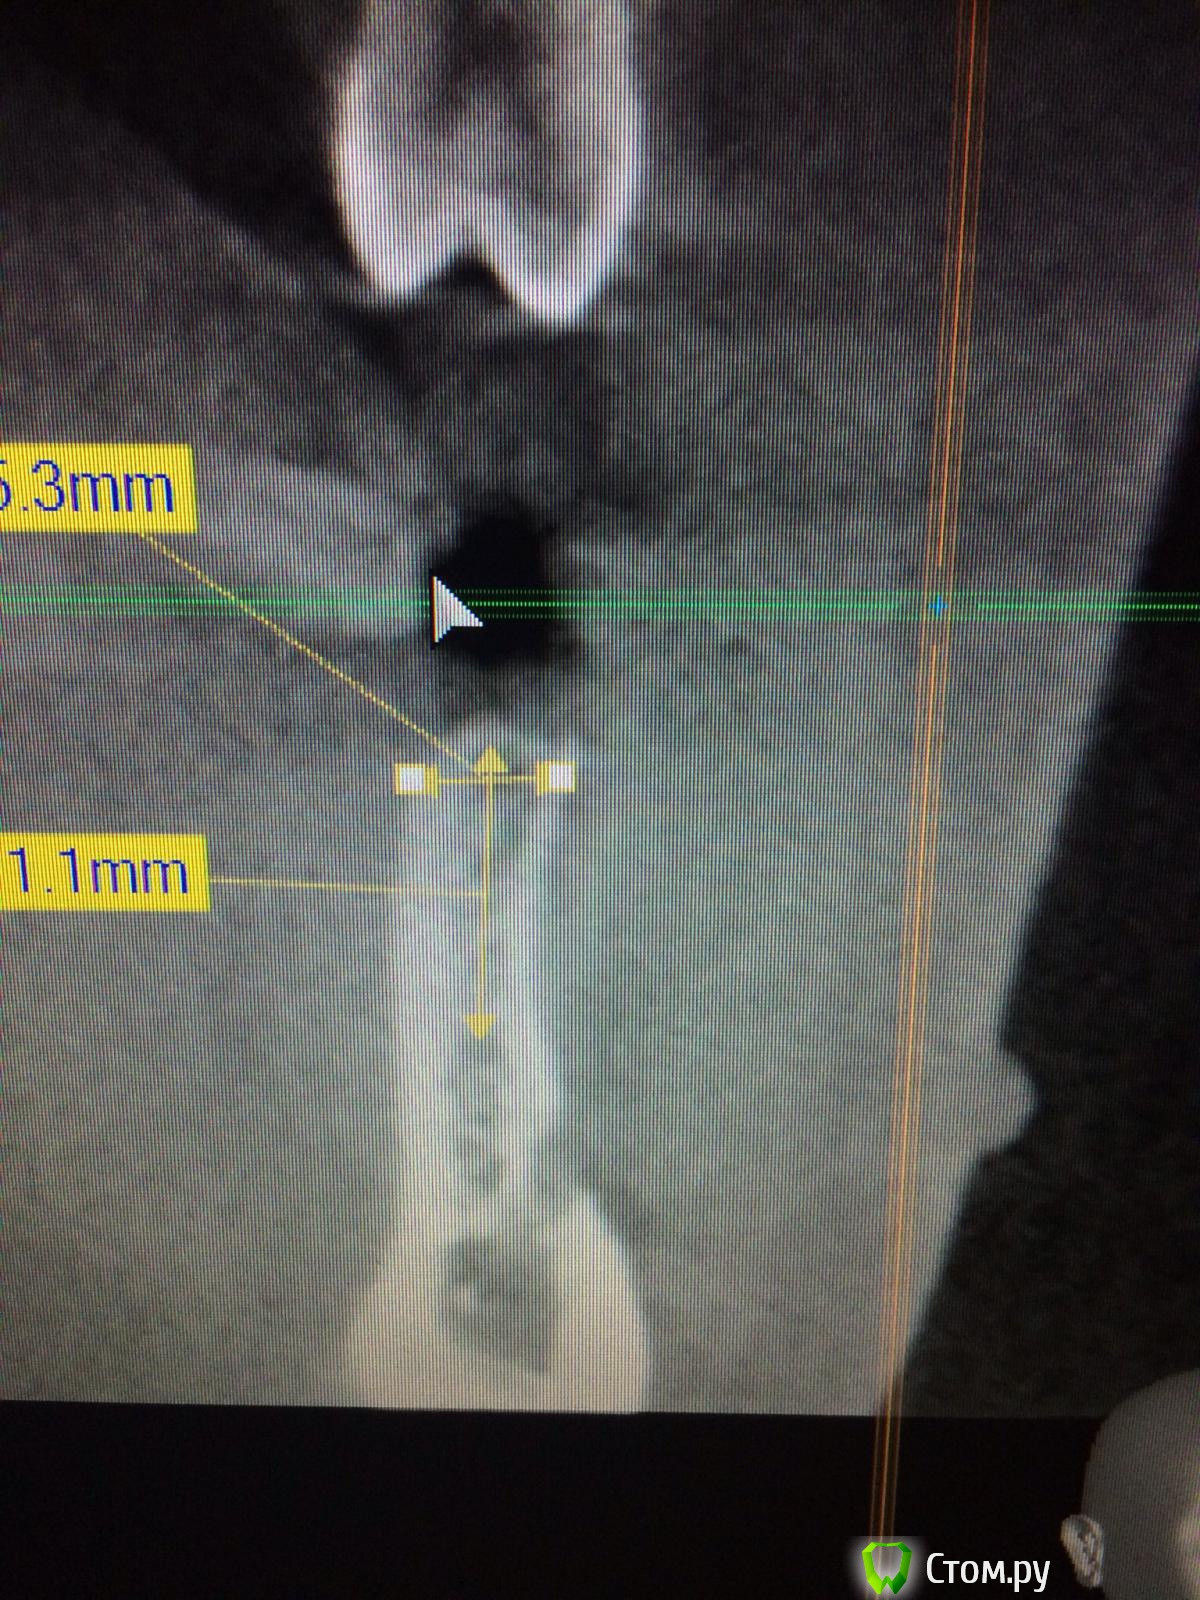

dr-krasnov Опубликовано 6 октября, 2014 Поделиться Опубликовано 6 октября, 2014 (изменено) image.jpg - это ватекЧто вы хотели показать? Изменено 6 октября, 2014 пользователем dr-krasnov Ссылка на комментарий

Vadim09 Опубликовано 6 октября, 2014 Поделиться Опубликовано 6 октября, 2014 Что вы хотели показать? Хотел показать разницу между ватек и планмека, к сожалению нет снимка поанмеки, потом скину Ссылка на комментарий